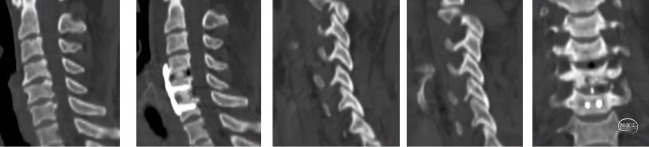

后纵韧带骨化:椎体次全切ACCF

如何防治椎体塌陷?

如何预防和治疗脑脊液漏?

椎体及骨化后纵韧带复合体

整体迁移融合技术ACAF